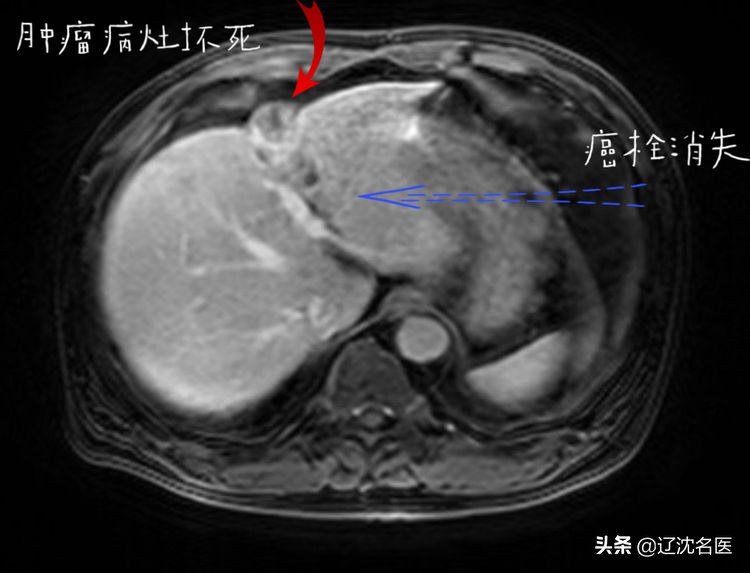

随后,患者与沈阳市第六人民医院肿瘤介入综合科行肝组织间粒子植入,及门脉癌栓内粒子植入治疗,共植入37颗粒子,术后恢复良好出院。2020年4月8日复查,肝增强MRI显示,病灶较前缩小,病灶内无明显强化,提示癌灶已坏死,门脉左右及主干支均通畅,肝门部及腹膜后淋巴结较前缩小。AFP 6.74 ng/ml,已降至正常。

粒子手术后4个月复查